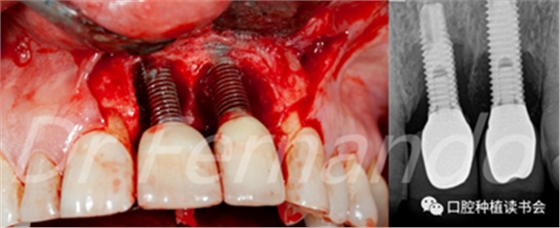

有的學者建議,作為診斷標準,在探診深度≥4 mm伴出血的情況下,種植體黏膜炎可以通過機械清創(chuàng)和洗必泰化學治療的保守治療方案治愈(1, 2) 。種植體周圍炎除涉及黏膜外,還涉及種植體周圍的骨組織。X光片診斷種植體周圍存在骨喪失,并伴有探診深度≥為5 mm和探診出血(圖2)

圖2 前牙美學區(qū)種植體周圍炎,出現(xiàn)明顯的骨喪失